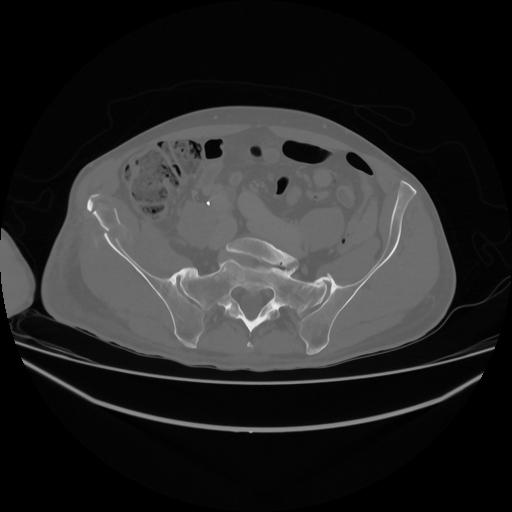

5 CUERPO,CE,Vol,1.0,CUERPO,,